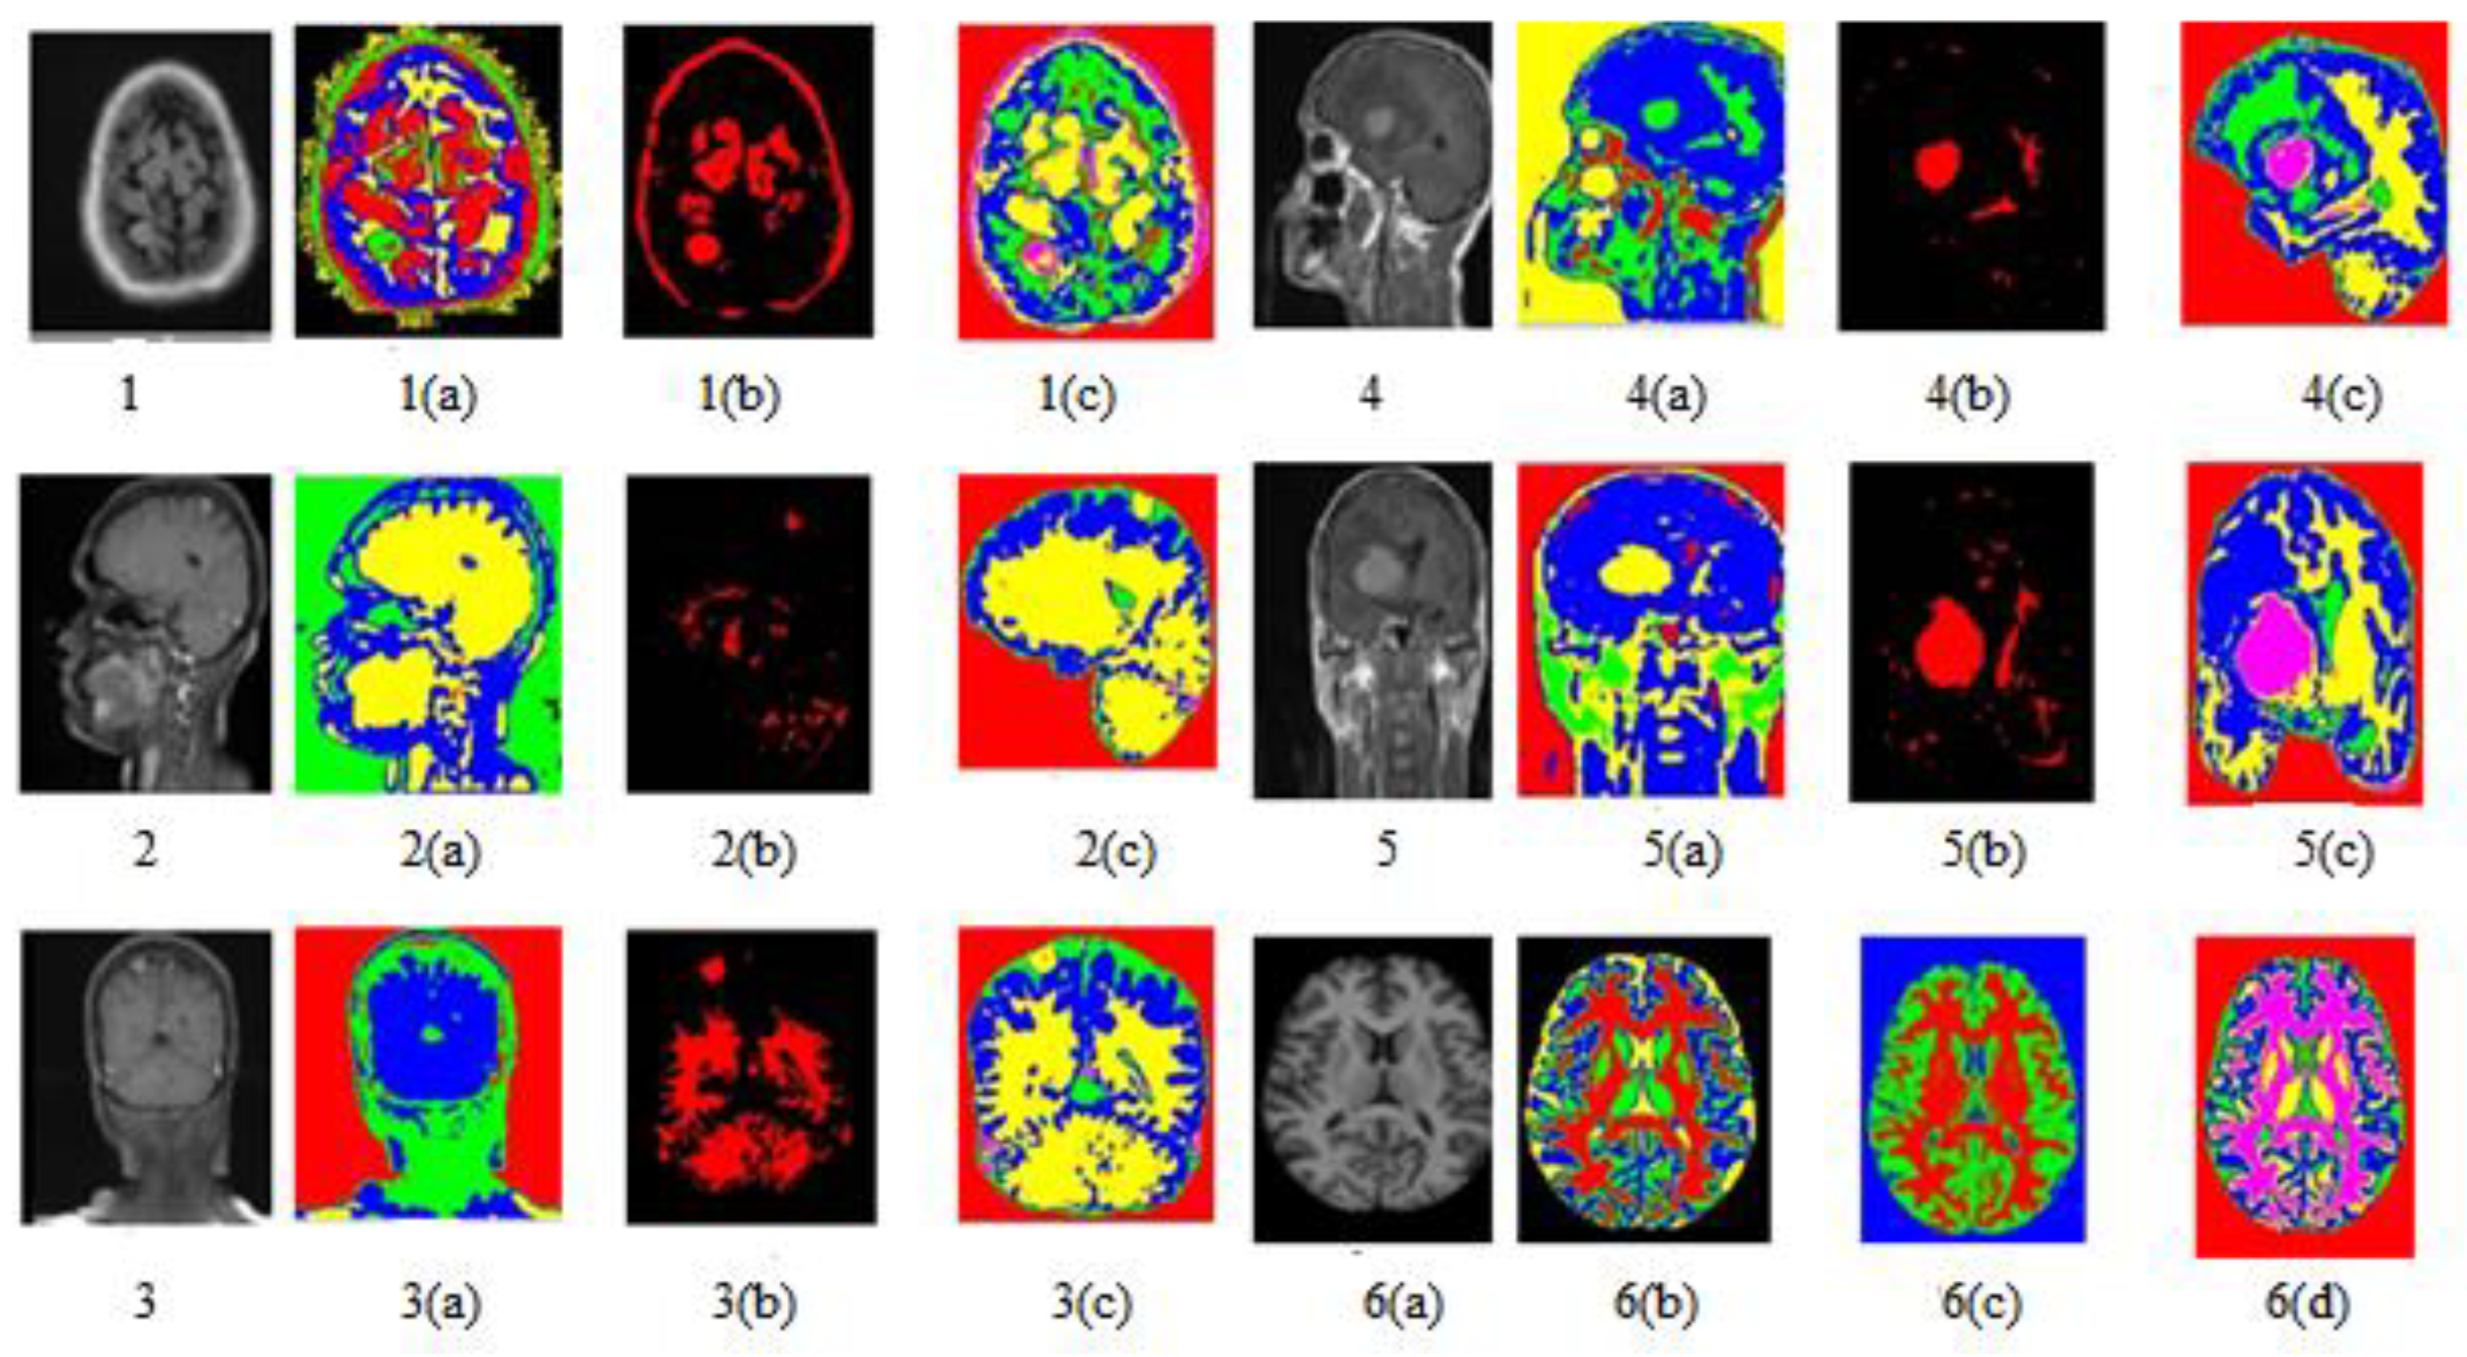

3.2.3. Clustering

3.2.4. Feature Extraction

3.3. Classification

4. Result and Analysis